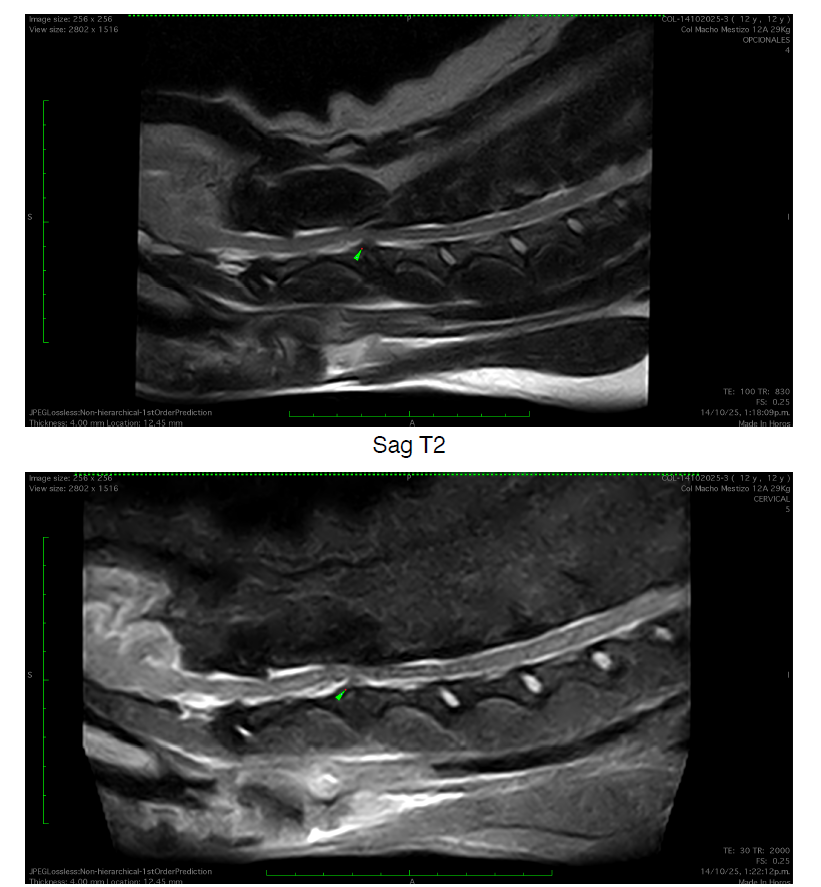

Hace poco tuvo una emergencia por una hernia discal y tuvieron que operarlo de urgencia para que no perdiera la movilidad.